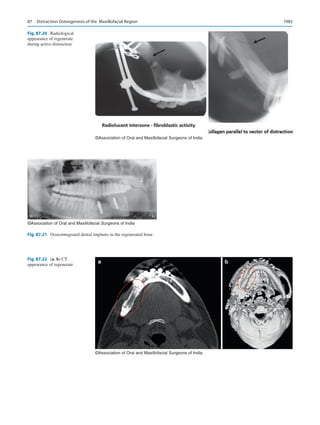

stresses importance on the physical examination of the air-

way [19]. While no single method can be deemed to be fool-